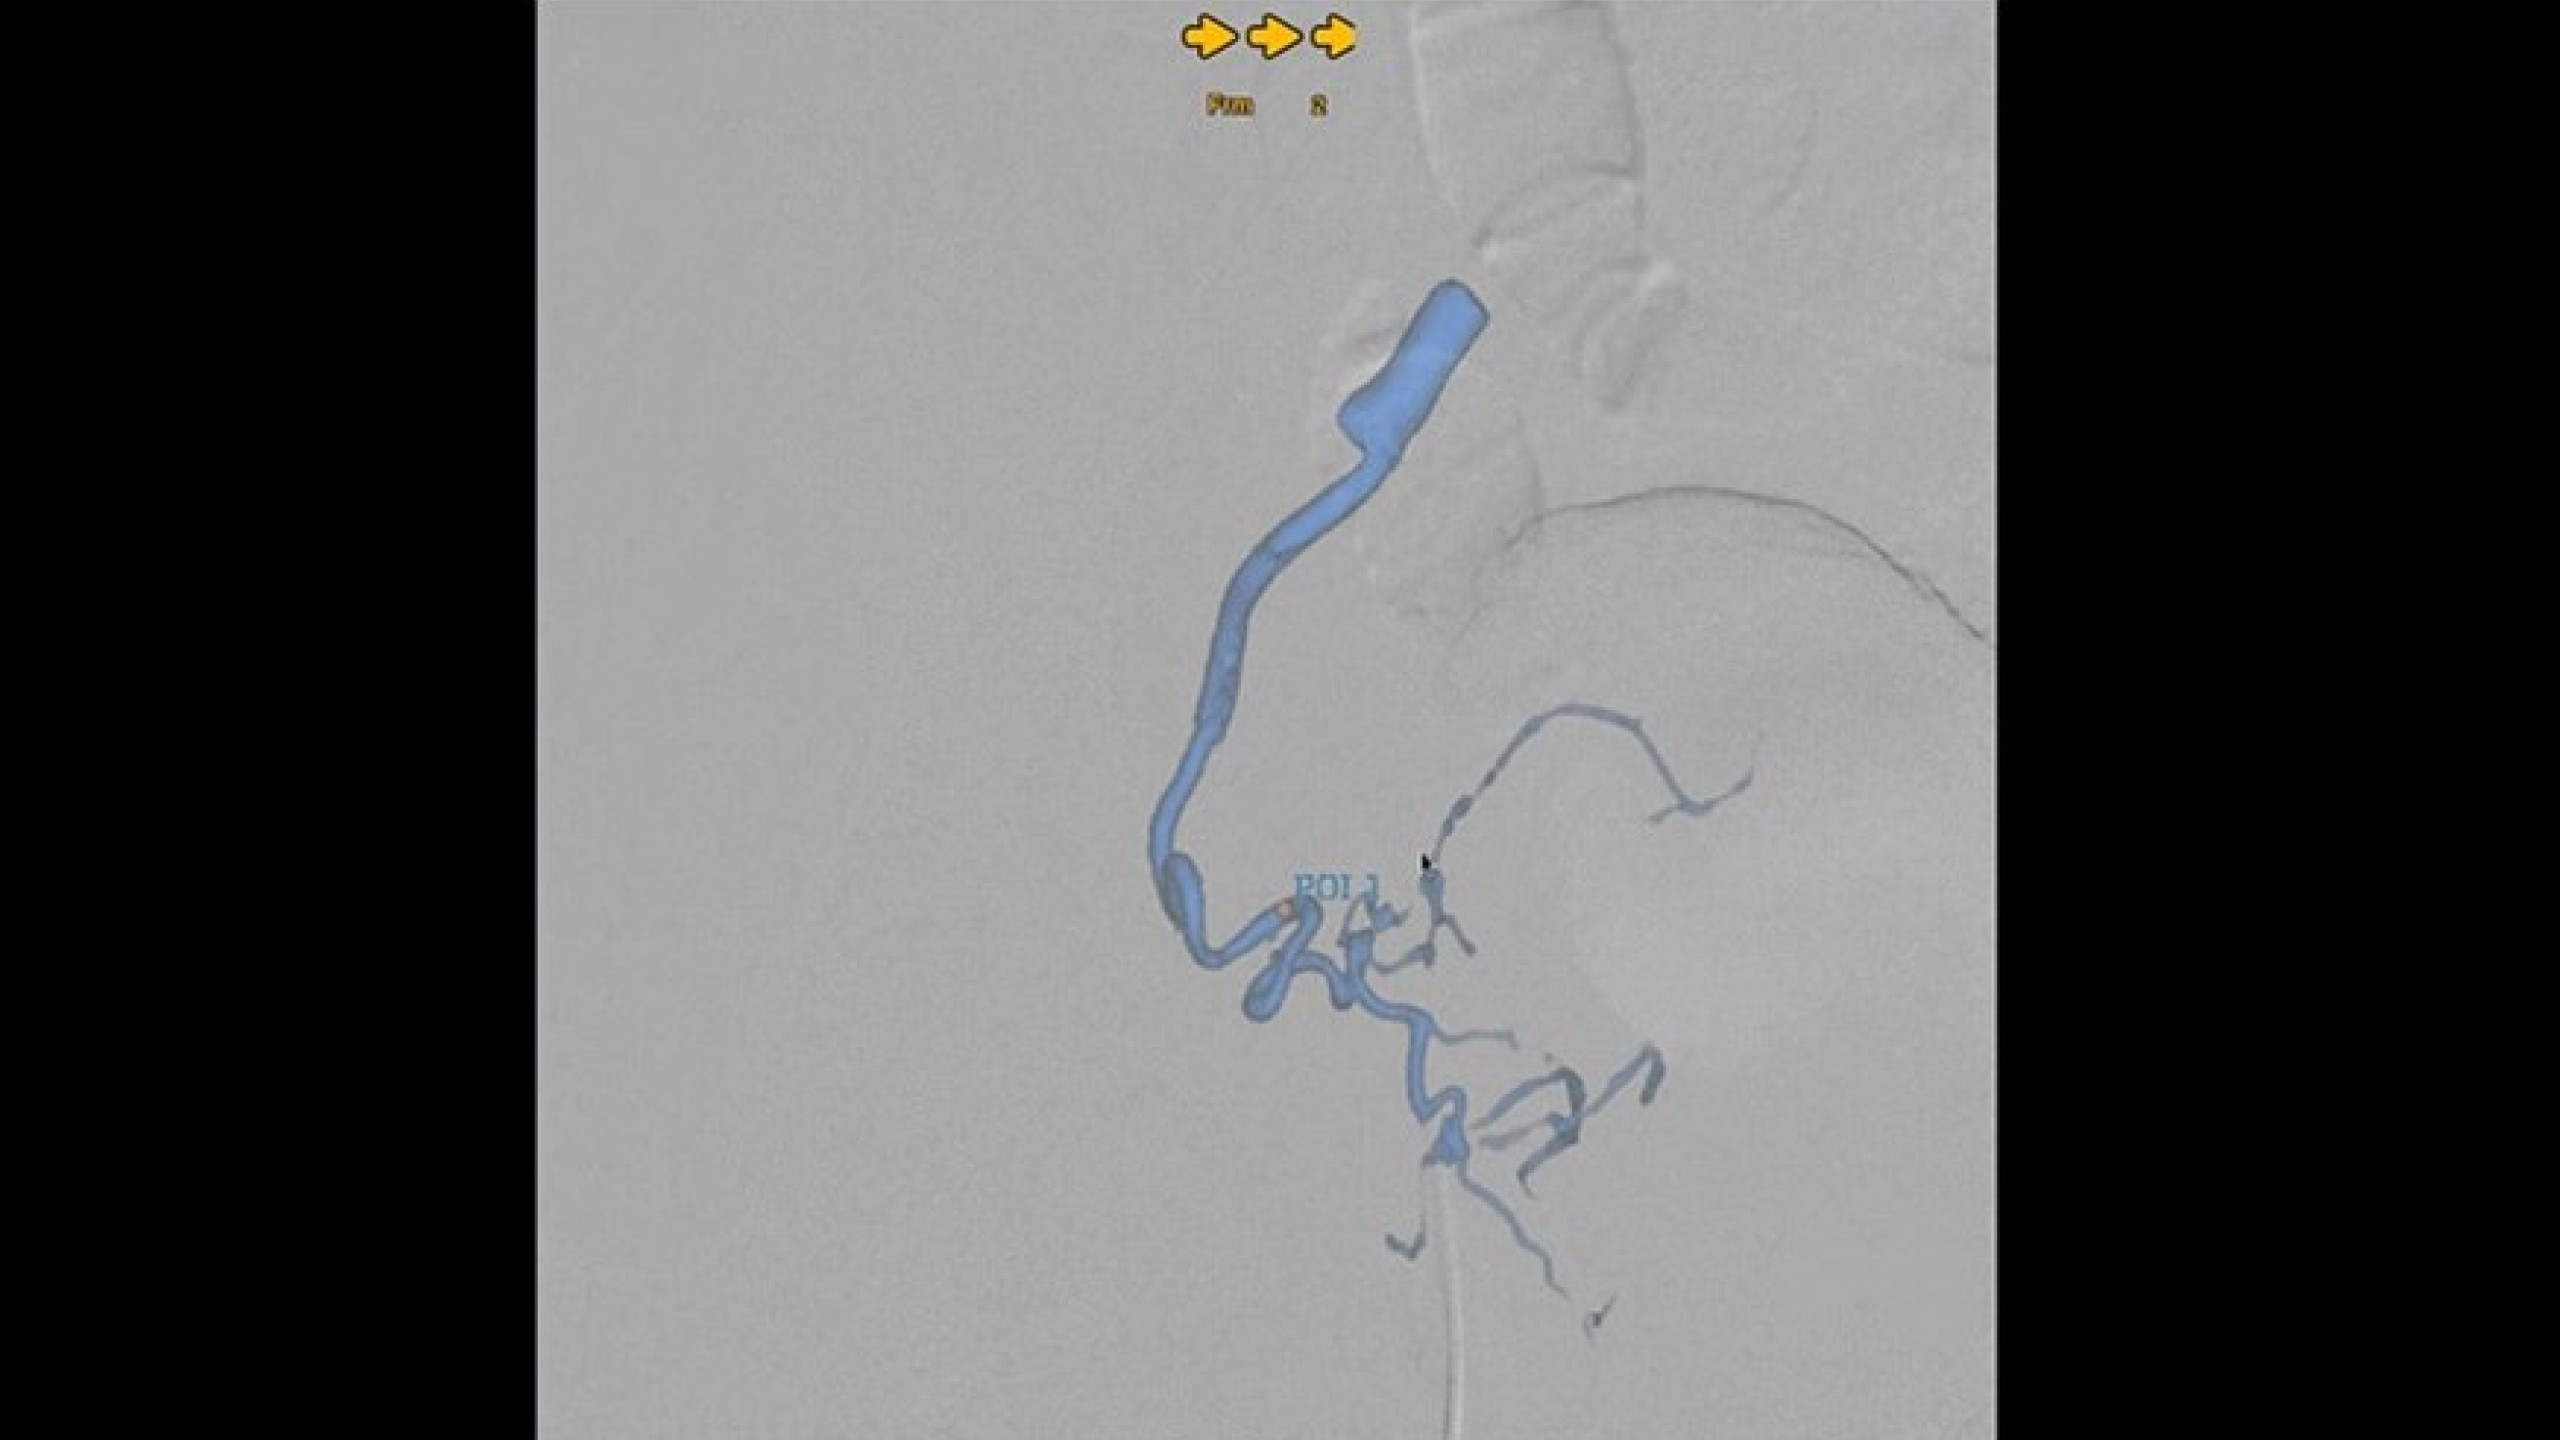

Embo ASSIST is an AI-based augmented guidance solution designed to define optimal embolization strategies and streamline your clinical workflow.

Dynamic simulation at different injection points

Augmented guidance